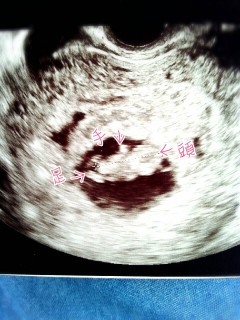

2人目の妊娠です(^^) 前回の健診から2センチ成長していました。 今回は手と足が生えてきており、 上の子の時には見れなかったけど、 今回は手足をはっきりと見る事が出来ました!! 上の子と同様つわりも無く親孝行なベビ(*^^*)笑 元気に産まれてきてね!